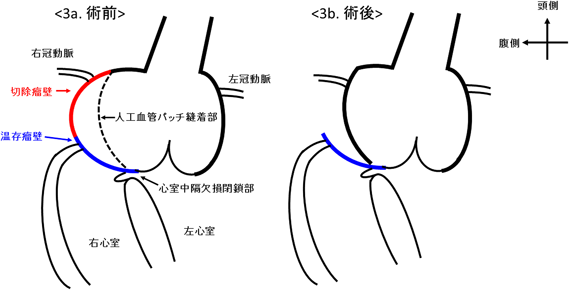

右バルサルバ洞瘤に対する手術例Surgical Repair of the Right Sinus of Valsalva Aneurysm Using an Artificial Vascular Graft Patch